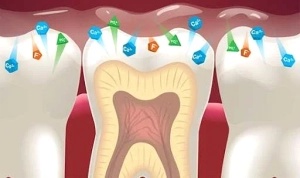

نقش واقعی فلوراید در محافظت از دندان ها

فلوراید مانند «معلم صبور» دندان ها عمل می کند — هر بار که مینای دندان در اثر اسیدهای تولید شده توسط باکتری ها دچار فرسایش می شود، فلوراید به ترمیم دوباره ساختار بلوری مینا کمک می کند. این فرآیند را Remineralization یا معدنی سازی مجدد می نامیم.

وقتی فلوراید وارد دهان می شود، به سطح دندان متصل می شود و ماده ای به نام فلورآپاتیت (Fluorapatite) تشکیل می دهد که در برابر اسید مقاومت بیشتری دارد.

در مرحله ری مینرالیزیشن از طریق بزاق، فعالیت باکتریواستاتیک فلوراید باعث کاهش فعالیت باکتری ها جهت تبدیل کربوهیدات ها به اسید می شود. در مرحله رشد و بلوغ مینای دندان، باعث قویتر شدن مینای می شود. فلورایدی که روزانه دریافت می کنیم باعث محافظت دندان از پوسیدگی می شود. فلوراید یک ماده طبیعی است که باعث افزایش مقاومت دندان ها در برابر پوسیدگی می شود.

1. تقویت مینای دندان: اولین خط دفاعی لبخند

مینای دندان مانند یک زره شیشه ای عمل می کند؛ زیبا، درخشان اما در معرض حمله دائمی اسیدها و باکتری ها. با مصرف فلوراید، ذرات این ماده وارد عاج و مینای دندان ها می شوند و باعث افزایش استحکام دندان و بالا رفتن میزان مقاومت آنها در برابر پوسیدگی می شوند. فلوراید با نفوذ در ساختار مینا، آن را به ترکیب مقاوم تری به نام فلورآپاتیت (Fluorapatite) تبدیل می کند. این ماده در برابر اسیدهای حاصل از غذاها و نوشیدنی های قندی تا سه برابر مقاوم تر از مینای طبیعی است. فلوراید مصرفی در داخل بزاق نهادینه می شود و اگرچه غلظت آن در بزاق کم است، اما غلظت آن در پلاک میکروبی زیاد است و باعث کاهش تولید اسید توسط میکروب ها می شود که به نوبه خود باعث کاهش ایجاد و گسترش پوسیدگی دندانی می شود.

معدنی سازی دندان ها

فلوراید در تعامل با دندان ها، ماده ای به نام فلوراپاتیت fluorapatite تشکیل می دهد که دندان ها را معدنی می کند. مینرالیزیشنMineralization یا معدنی کردن، فرآیند سخت شدن شیمیایی است، اثری که از دمینرالیزیشن (تجزیه مواد معدنی) دندان جلوگیری می کند. جالب اینجاست که، گرچه فلوراپاتیت بخش طبیعی دندان ها نیست، اما مفید است و باعث بروز هیچ آسیبی به دندان ها نمی شود.

معدنی شدن فلوراپاتیت ناشی از مکمل های فلوراید همچنین به دندان ها کمک می کند تا در برابر آسیب هایی که می توانند توسط غذا، نوشیدنی ها و باکتری ها وارد شوند مقاومت کنند.